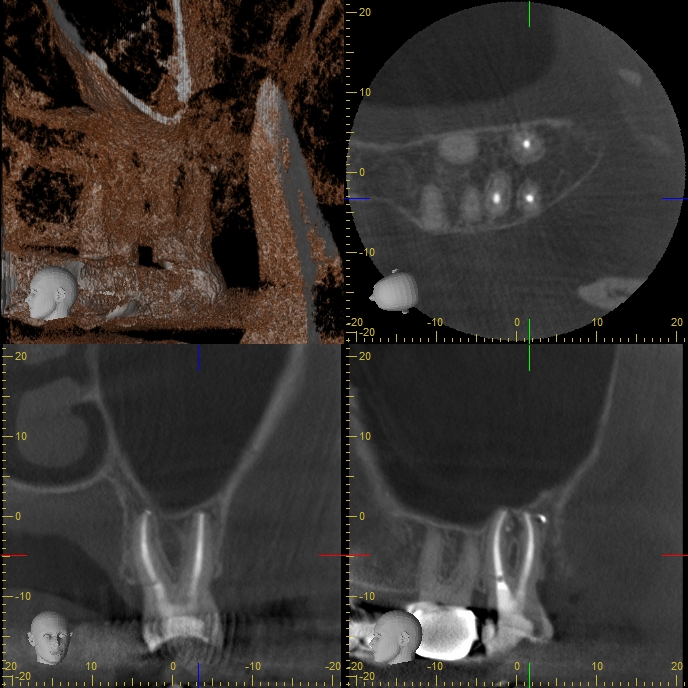

27AA2yrecall Veröffentlicht 6. Mai 2014 am 688 × 688 in Massive apikale Aufhellung an Zahn 27 im Recall DVT Screenshot 2 Jahre post WF